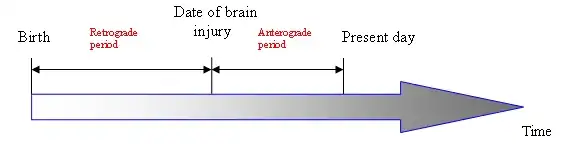

Some researchers prefer to consider the hippocampus as part of a larger medial temporal lobe memory system responsible for general declarative memory (memories that can be explicitly verbalized — these would include, for example, memory for facts in addition to episodic memory). Some evidence supports the idea that, although these forms of memory often last a lifetime, the hippocampus ceases to play a crucial role in the retention of the memory after a period of consolidation. Damage to the hippocampus usually results in profound difficulties in forming new memories (anterograde amnesia), and normally also affects access to memories prior to the damage (retrograde amnesia). Although the retrograde effect normally extends some years prior to the brain damage, in some cases older memories remain intact - this sparing of older memories leads to the idea that consolidation over time involves the transfer of memories out of the hippocampus to other parts of the brain. However, researchers have difficulties in testing the sparing of older memories and, in some cases of retrograde amnesia, the sparing appears to affect memories formed decades before the damage to the hippocampus occurred, so its role in maintaining these older memories remains controversial.

As already mentioned in the preceding section about the hippocampus, there are two types of amnesia - retrograde and antrograde amnesia.